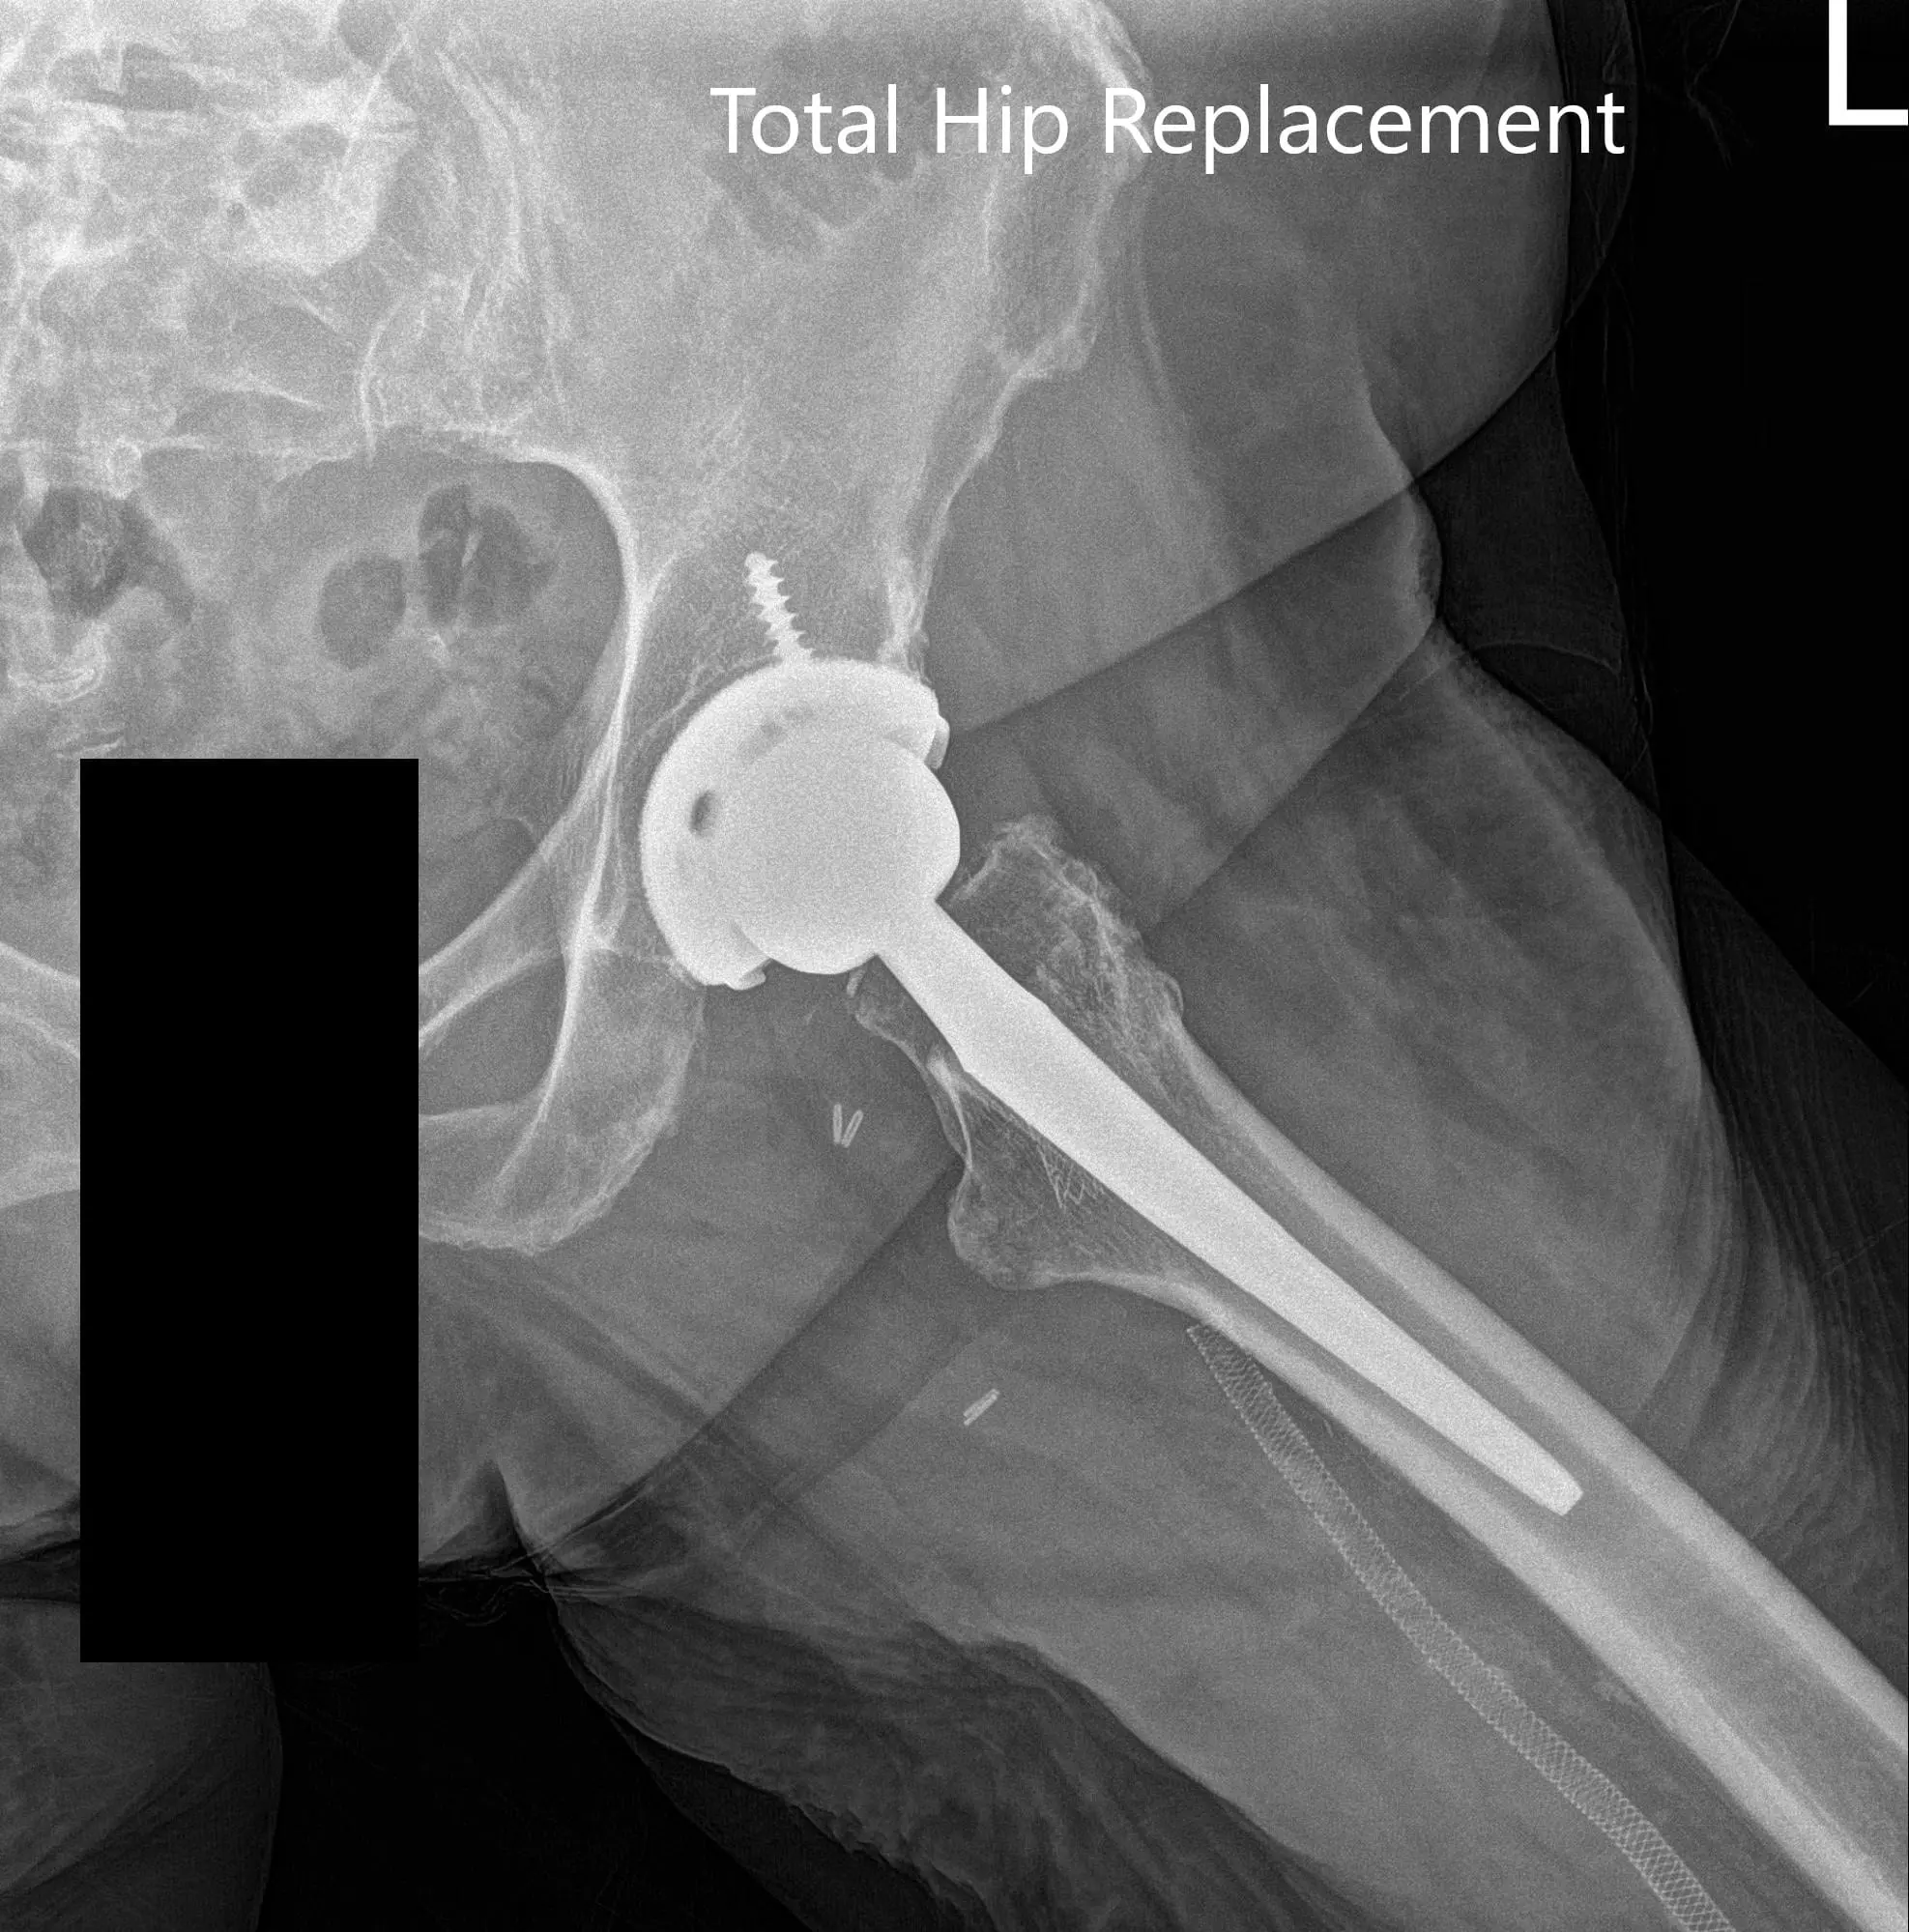

The implant used: Titanium hemispherical shell 60 mm with a 6.5 cancellous screw, 6.5 mm in diameter, 25 mm in length with ceramic femoral head 36 mm, 0-degree polyethylene with 127-degree neck angle hip stem size 5.

Postoperative X-ray images showing AP and lateral images